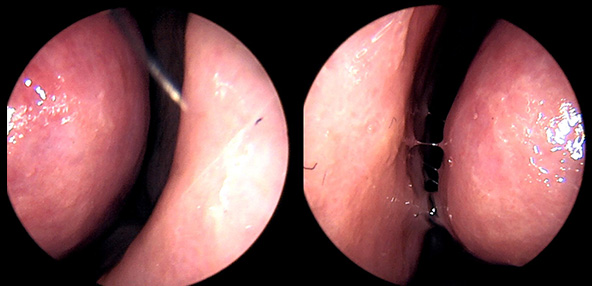

※ 비중격 비염 수술 후 생길 수 있는 부작용으로는 출혈, 감염, 염증이 있을 수 있습니다.

본 사진은 의료기관에서 진료를 본 환자이고, 전후 사진 인물이 동일인이며,동일조건에서 촬영이 되었습니다.